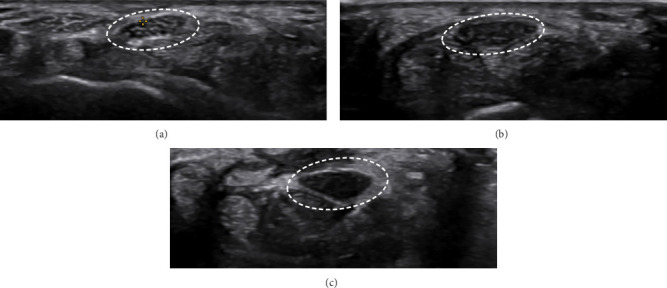

目的:本研究旨在评估各种超声标准对腕管综合征(CTS)严重程度分级的价值。方法:由经验丰富的放射科医生对确诊的CTS患者进行超声评估,对NCS结果不知情。测量旋前方肌横截面积(CSA)、腕管进出口、回声性、屈曲时的横向运动、压平率和屈肌支持带增厚。结果:正中神经回声减弱是轻度和中度病例的显著特征。神经运动减少在严重的CTS病例中更为普遍。两组正中神经压平率和屈肌视黄带厚度无显著差异。进气道弯曲有显著性差异。进口和出口的CSA显示严重的CTS,差异有统计学意义。结论:虽然正中神经压平率和屈肌视黄带厚度无明显差异,但超声多指标对准确诊断和治疗具有重要意义。

Objective: This study aimed at assessing the value of a variety of ultrasound criteria for grading carpal tunnel syndrome (CTS) severity. Methods: Ultrasound evaluations were conducted on confirmed CTS patients by an experienced radiologist, blinded to NCS results. Cross-sectional area (CSA) at pronator quadratus muscle, carpal tunnel inlet and outlet, echogenicity, transverse motion during flexion, flattening ratio, and thickening of the flexor retinaculum were measured. Results: Decreased echogenicity of the median nerve was notably observed as a distinguishing feature between mild and moderate cases. Decreased nerve movement was significantly more prevalent in severe CTS cases. No significant differences were found in the median nerve flattening ratio or flexor retinaculum thickness. Bowing at the inlet showed significant differences. CSA at the inlet and outlet indicated severe CTS with significant differences. Conclusion: The findings highlight the importance of using multiple sonographic criteria for accurate diagnosis and treatment, although no significant differences were noted in the median nerve flattening ratio and flexor retinaculum thickness.